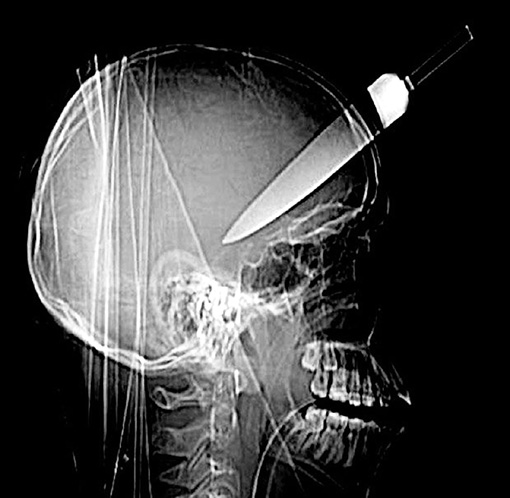

4. Вытаскивать нож из раны

Почему. Может открыться сильное кровотечение.

Правильно. Срочно вызвать медиков, которые доставят травмированного человека в операционную. Бояться инфекции смысла нет: она уже внутри раны, с ней будут бороться, когда извлекут посторонний предмет и остановят кровь.